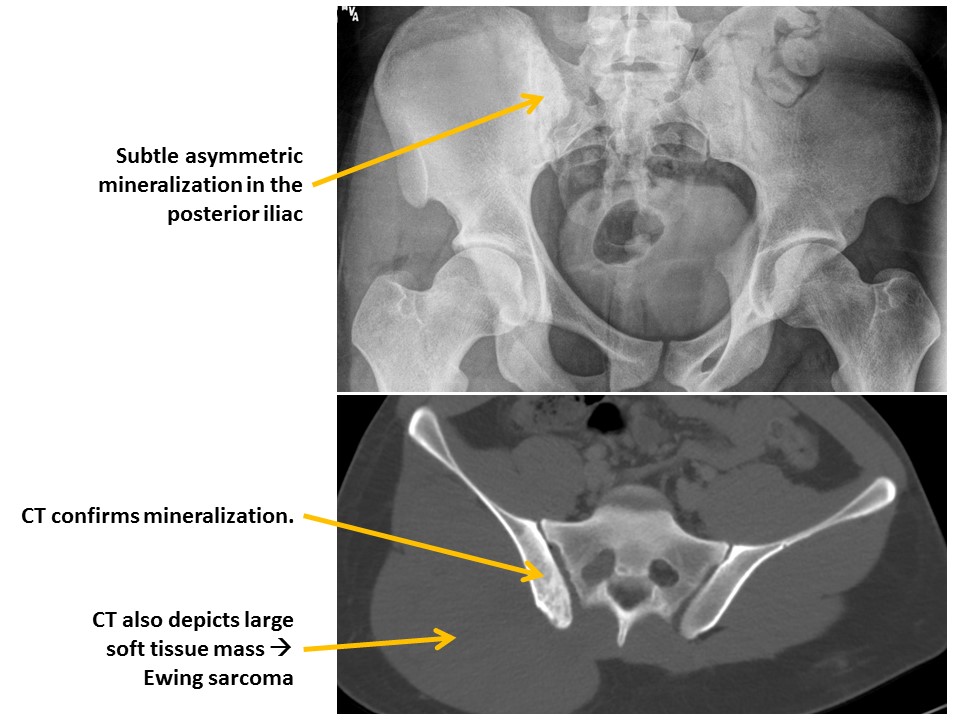

ILIAC BONES

Posterior iliac bone fractures are present. [Yes/No]

The osseous mineralization is diffusely abnormal. [Yes/No]